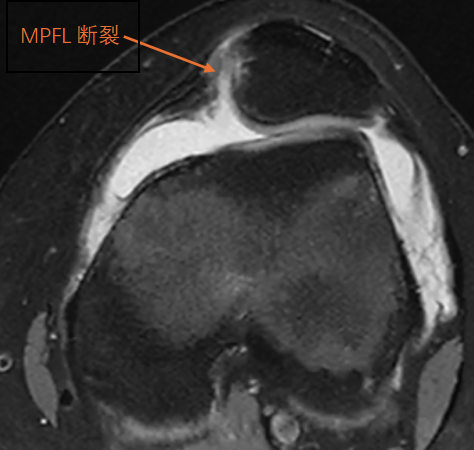

3、MRI:

最常用的评估髌股关节软组织和滑车软骨的检查。

MRI 在发现 MPFL 损伤时具有 85% 的敏感性和 70% 的准确性,其特征性表现包括 X 线不能发现的软骨损伤及髌骨内侧面和股骨外侧髁的骨挫伤。

1、内侧髌股韧带(MPFL)重建术:在膝关节0°- 30°屈曲时,MPFL是限制髌骨向外侧移位最主要的韧带,其发生损伤(撕裂、拉伸)时会导致髌骨失去稳定向外侧脱位,因此,髌骨脱位时要行MPFL重建术。